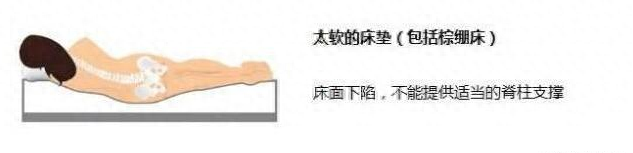

5. 睡软硬适中的床

当床过软时,在腰臀重量的压力下,形成了腰臀部下陷、头部腿部两边高的体位。使得脊柱无法得到适当的支撑,腰部肌肉一直处于拉伸状态,无法得到充分的休息。所以,过软的床不适合腰椎间盘突出患者。